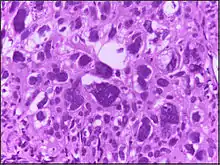

Large cell

Large cell is a term used in oncology. It does not refer to a particular type of cell; rather it refers to cells that are larger than would be normally expected for that type. It is frequently used when describing lymphoma and lung cancer.

The phrase giant cell is also frequently used, especially with carcinoma.